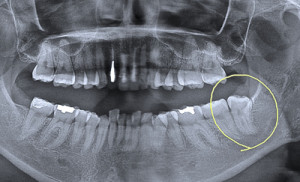

親知らずをお口全体のレントゲンでチェック

コラム「親知らずをお口全体のレントゲンでチェック」の画像